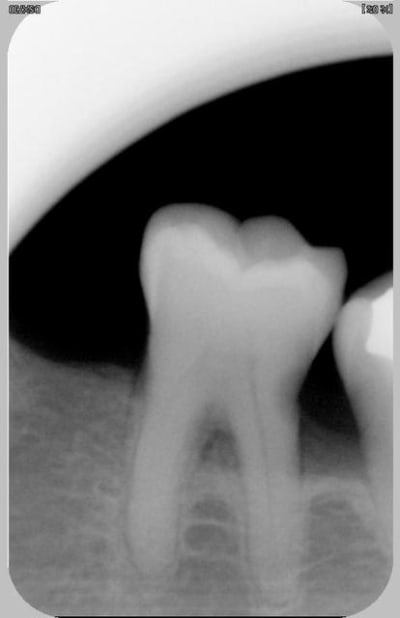

pas sûr pour la carie mais sinon je pense qu'il s'agit d'un syndrôme septum faut leur apprendre à faire soins locaux avec brossettes

si la douleur vient d'une inflammation infection donc d'une compression je prescris solupred(1à3)par jour sur 3 jours plutot le matin et abique

pour le diagnostic plus precis sondage paro interradiculaire /evaluation pulpaire etc...

nettoyage aux US, apprentissage de la brossette, soin de la carie ( comme tu peux), et tu vois à deux semaines pour juger du tissu osseux.